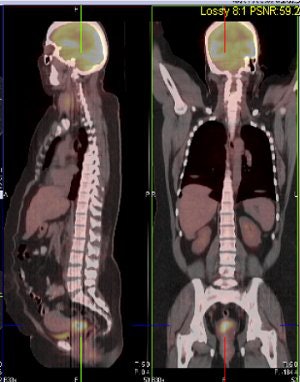

| Above and below, representative images of a 39-year-old patient, currently undergoing treatment, with FIGO stage IB2 squamous cell carcinoma of the cervix. Pretreatment FDG-PET/CT identified an FDG-avid cervical tumor mass plus bilateral iliac and right common iliac metastatic lymphadenopathy. Images courtesy of Dr. Julie Schwarz, Ph.D. |

Twenty-five patients with advanced-stage cervical cancer were included, all of whom were treated with chemoradiation. Whole-body FDG-PET scans were done and co-registered with CT scans. Twenty-eight pretreatment tumor biopsies were done, and pathologic review confirmed the presence of invasive cancer in 26 of 28 cases.